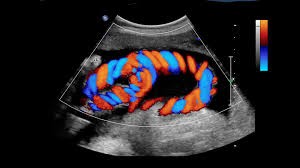

A colour doppler ultrasound is a non-invasive imaging test that uses sound waves to examine blood flow through your arteries and veins. Unlike a regular ultrasound, a doppler gives you more data — it shows how blood moves, how fast, and whether there are any blockages or narrowing, which helps doctors assess vascular health. It’s useful in diagnosing problems in the heart, major vessels, limbs, kidneys, liver, etc.

4. As part of prenatal care (for blood flow in placenta or umbilical cord)

Sadhu Vaswani Mission Medical Centre provides several types of Doppler studies to meet these needs: obstetric colour doppler, carotid/vertebral artery doppler, peripheral vascular doppler, renal doppler, testicular doppler, etc.